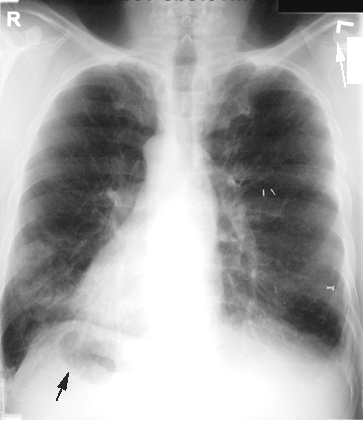

Хоёр уушигны суурь хэсэгт байрласан олон тооны хий, шингэний түвшин бүхий хөндийнүүд

Гуурсан хоолойн тэлэгдэл.